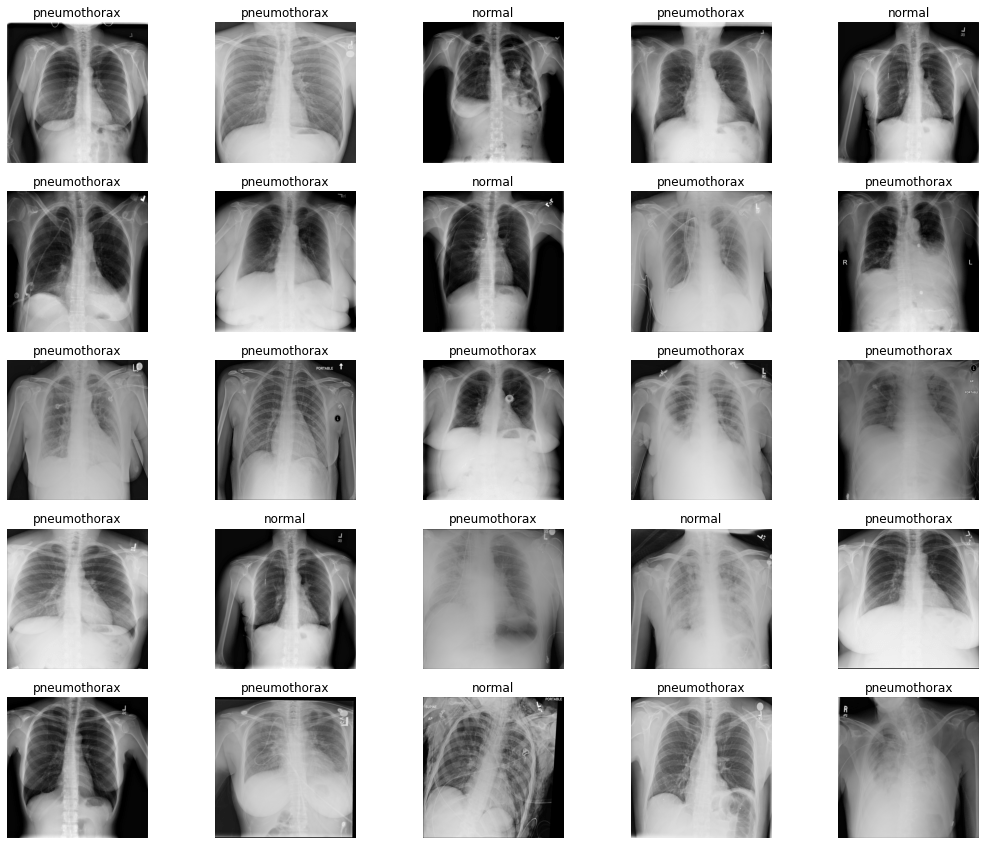

Pneumothorax Binary Classification using PyTorch Model Pretrained on Medical Image Classification Datasets Covering primary data modalities in biomedical images, medmnist v2 is designed to perform classification on lightweight 2d and 3d. 154 papers with code • 9 benchmarks • 13 datasets. A list of medical imaging datasets. Medical image and video datasets can support biomedical research through training machine learning algorithms, particularly via image recognition and classification. Covering primary data modalities in. Medical Image Classification Datasets.

Pneumothorax Binary Classification using PyTorch Model Pretrained on Medical Image Classification Datasets 154 papers with code • 9 benchmarks • 13 datasets. Covering primary data modalities in biomedical images, medmnist is designed to perform classification on lightweight 2d and 3d images. Covering primary data modalities in biomedical images, medmnist v2 is designed to perform classification on lightweight 2d and 3d. A list of medical imaging datasets. Covering primary data modalities in biomedical. Medical Image Classification Datasets.